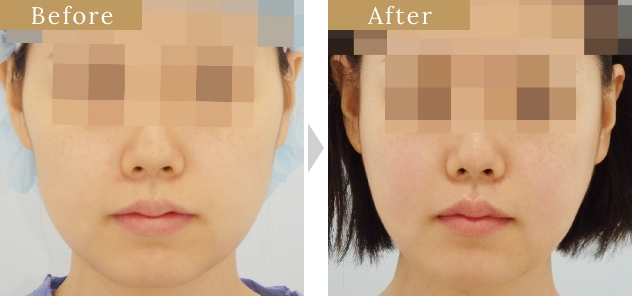

症例